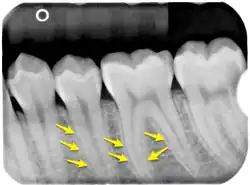

Radiological appearance

The lamina dura is a dense bone structure visible on dental radiographs as a thin, radiopaque border adjacent to the periodontal ligament and alveolar crest, forming part of the tooth socket.[10][11] Its role as "bundle bone" stems from its dense composition containing Sharpey's fibers, which develops during tooth formation as an egg-shell-like envelope and persists after eruption as a radiopaque layer.[10][8] Rather than being a radiographic artifact, studies confirm its appearance is determined by both structural properties and X-ray beam direction.[12][8] Several factors influence its radiographic visibility, including tooth position, root number, condition of the periodontal ligament, X-ray beam angulation,[13] anatomical structure superimposition, and film exposure times.[14] These variables can cause irregular appearances or apparent discontinuity, particularly in maxillary molars and premolars. Proper X-ray angulation, allowing rays to pass tangentially through the structure, enhances its visibility, while improper alignment or altered anatomy can obscure its appearance.[8][13]